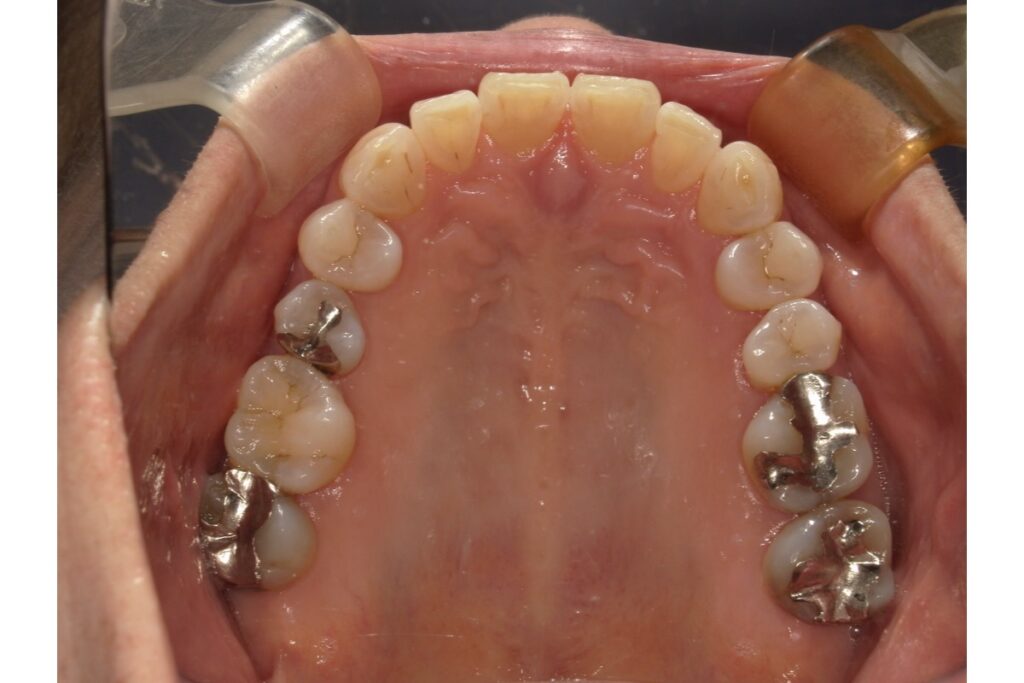

5.症例紹介

実際に補綴物の入っている治療の症例をご紹介します、インビザラインにて治療されました。

治療期間は約1年です。